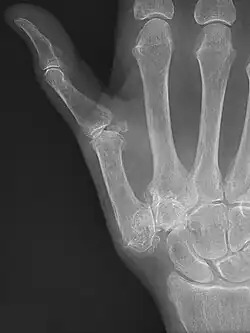

Trapeziometacarpal osteoarthritis (TMC OA) is, also known as osteoarthritis at the base of the thumb, thumb carpometacarpal osteoarthritis, basilar (or basal) joint arthritis, or as rhizarthrosis.[3][1][2] This joint is formed by the trapezium bone of the wrist and the metacarpal bone of the thumb. This is one of the joints where most humans develop osteoarthritis with age.[4] Osteoarthritis is age-related loss of the smooth surface of the bone where it moves against another bone (cartilage of the joint).[3][5] In reaction to the loss of cartilage, the bones thicken at the joint surface, resulting in subchondral sclerosis. Also, bony outgrowths, called osteophytes (also known as "bone spurs"), are formed at the joint margins.[6]

TMC OA is diagnosed based on symptoms and signs.[8] Radiographs can confirm the diagnosis and the severity of TMC OA. Other diagnoses in this region include scaphotrapezial trapezoid arthritis and first dorsal compartment tendinopathy (De Quervain syndrome) although these are usually easy to distinguish.